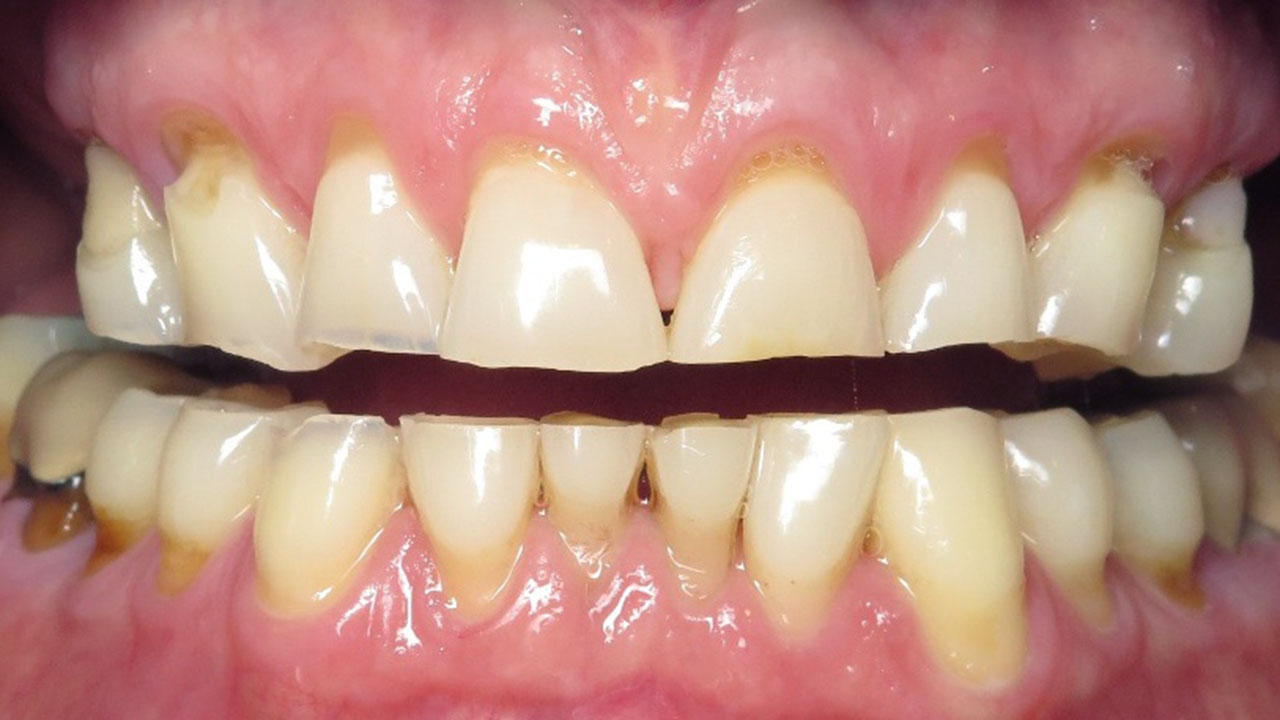

The patient was referred by his periodontist after being told that severe tooth grinding had worn his teeth down significantly and that he could lose his teeth if he did nothing to restore them.

Hopeless lower teeth were removed and the remaining teeth were restored with all-ceramic crowns to rebuild the bite and protect the worn dentition.

This patient was referred by his periodontist after severe tooth grinding had worn his teeth down significantly. He had already lost several teeth, and the remaining lower back teeth had a poor long-term prognosis if the bite was not restored.

Treatment was completed in stages. The upper teeth were restored first with all-ceramic crowns to rebuild the bite. After a pause to allow the patient time for physical and financial recovery, treatment continued with restoration of the lower teeth.